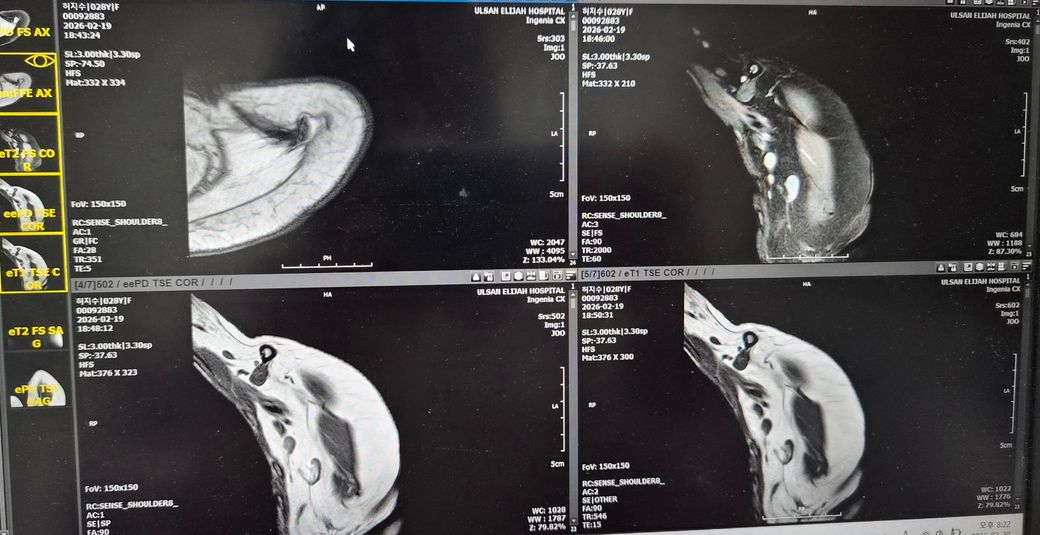

어께MRI판독좀 해주세요!어떤가요?

제가 2024년도 어께로 넘어진 이유로 1년10개월동안 아파서 MRI찍고 무섭다고해서

뺄수밖에 없었어요.누워서 안정취하다가 수납하고갔어요.그다음날 종합병원정형외과가서 접수하고 기다렸어요. 들어갔더니 의사가 힘줄에는 다 이상이 없데요.뼈가 (견봉쪽?)골절되면서 붙으면서 뼈가 위로조금 오른쪽이랑 다르게 올라갔데요 그래서 아프면 주사맞자고해서 주사대기중이였어요.옷갈아입고 기다렸어요.

올려주신 MRI사진은 화면 촬영본이라 정확한 판돈까지는 어렵지만, 담당 의사가 말씀하신 것처럼 회전근개 힘줄 자체의 명확한 완전파열 소견은 없어 보이는 경우로 이해됩니다. 설명해주신 내용상 어깨 위쪽 뼈 쪽 골절이 치유되는 과정에서 약간 위로 붙어 형태가 변형되었고, 그로인해 어깨를 들때 힘줄과 뼈 사이 공간이 좁아져 마찰이 생기는 충돌 증후군 형태일 가능성이 높아 보입니다. 주사 치료는 보통 염증을 줄이기 위한 스테로이드+국소 마취제 주사이며, 약물이 하얗고 양이 많으며 들어갈때 아픈것은 비교적 흔합니다. 주사 맞은 당일저녁에 헬스장에서 찌릿한 통증이 생긴것은 힘줄이 새로 찢어졌다기보다는 주사 후 자극+기존 충돌부위 자극 때문일 가능성이 훨씬 큽니다. 현재로서는 최소 1주일 정도는 상체웨이트 운동을 쉬고, 얼음찜질과 가벼운 가동범위 운동만 하는것이 좋습니다. 이후 통증이 줄어들면 가벼운 밴드 운동부터 재개하는 것이 안전합니다. 빠른쾌유를 빕니다!

올려주신 사진은 정확한 컷이 아니라 판독이 어렵습니다

올려주신 내용 따르면 견쇄부위 언급이 있습니다

쇄골을따라가면서.견쇄관절 볼록 나온 부분에 압통이 있으신 지 확인해보시면 좋을 것 같아요